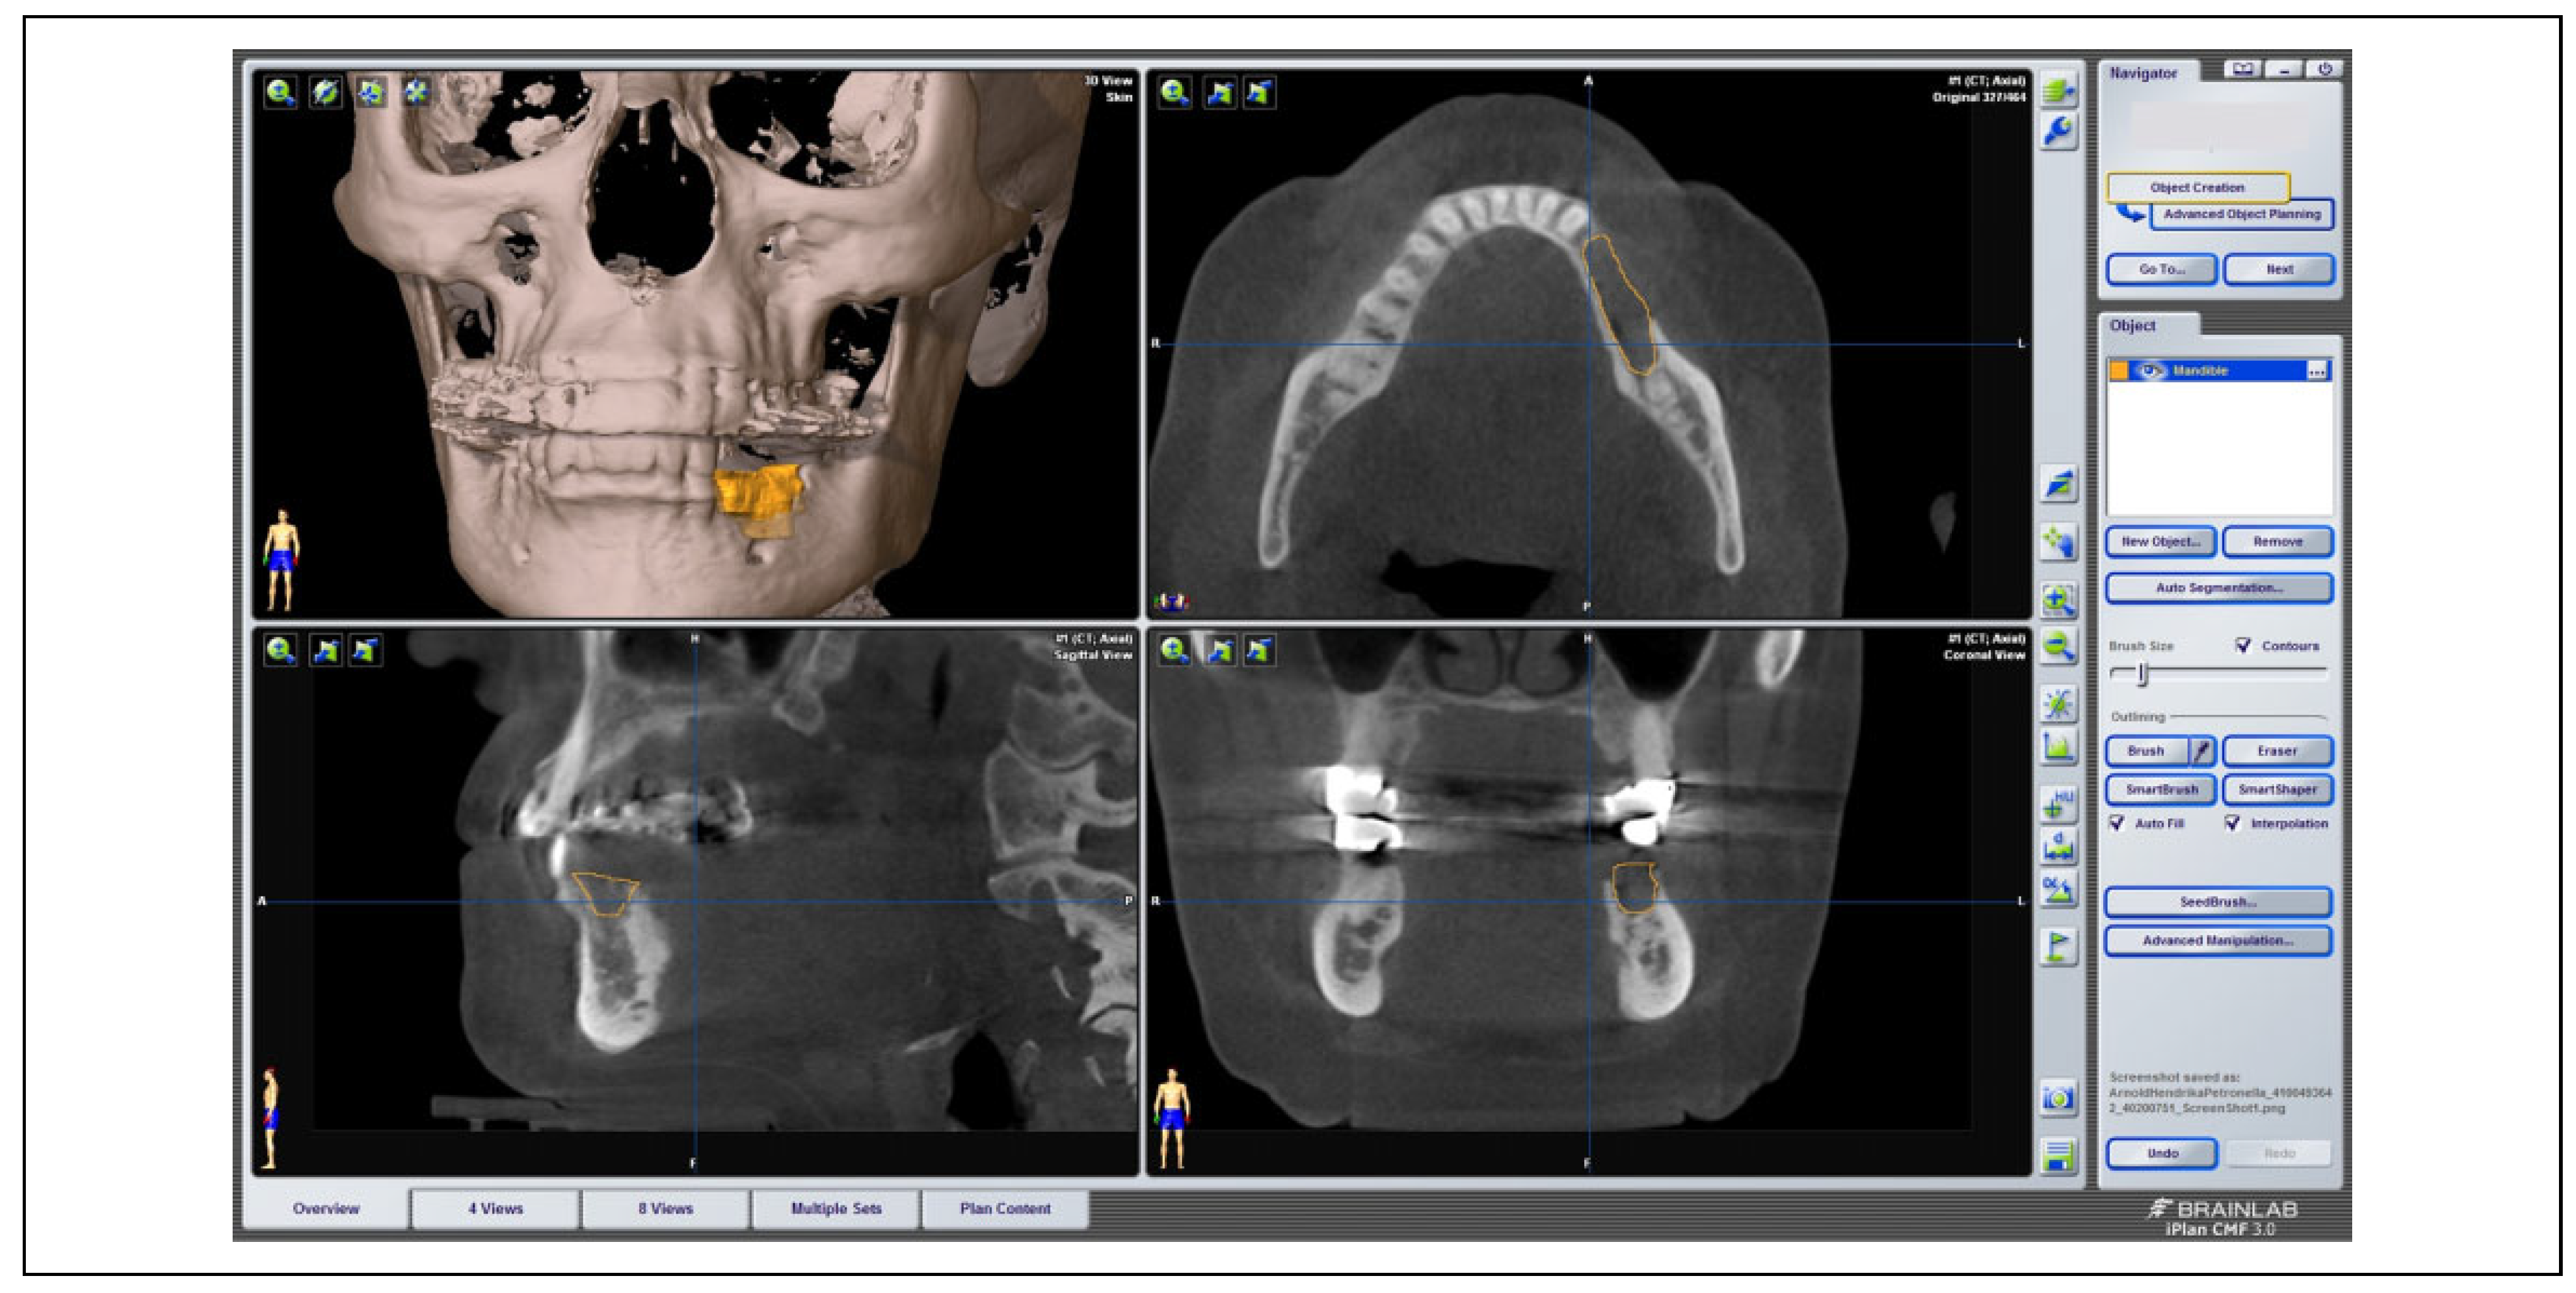

On the basis of 3D DICOM data sets of 175 patients suffering from MRONJ, the size of the necrosis was investigated using the software iPlan 3.0.5 (BrainLAB AG) (see

Figure 1). Via the “brush” tool, the outline of the necrosis was marked manually layer by layer in the axial view and thoroughly adjusted in the sagittal as well as coronal view if needed. Segmentation was performed for each patient 1 to 3 times for internal control. Exact cubic numbers of the virtually reconstructed 3D volume of necrosis was then determined via the “plan content” tool.